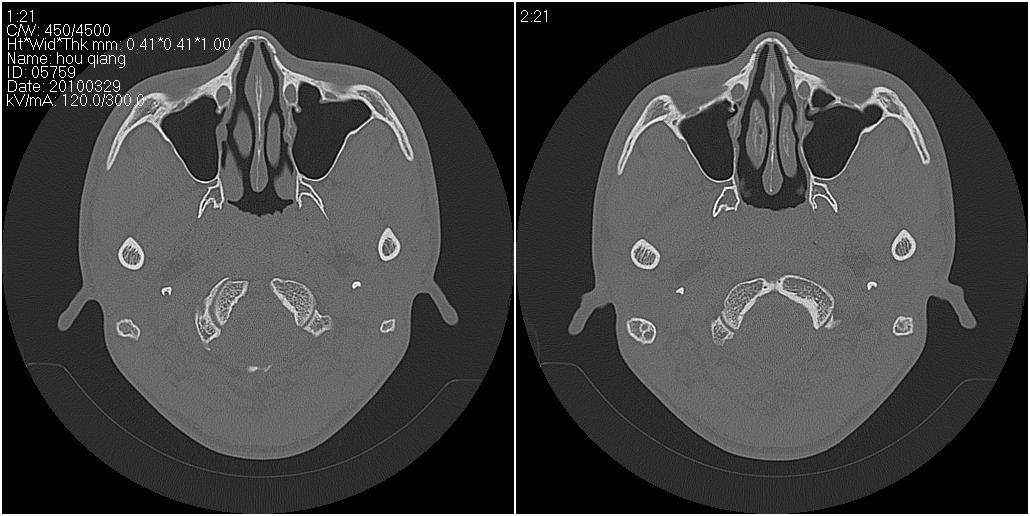

标题: CT25419:男性,18岁。右耳肿、痛5个多月。 [打印本页]

标题: CT25419:男性,18岁。右耳肿、痛5个多月。

右侧中耳乳突炎累及外耳道,鼻咽腺样体肥大。

1)右侧慢性中耳乳突炎并右侧中耳腔及外耳道肉芽肿或胆脂瘤形成。2)鼻咽腺样体肥大。